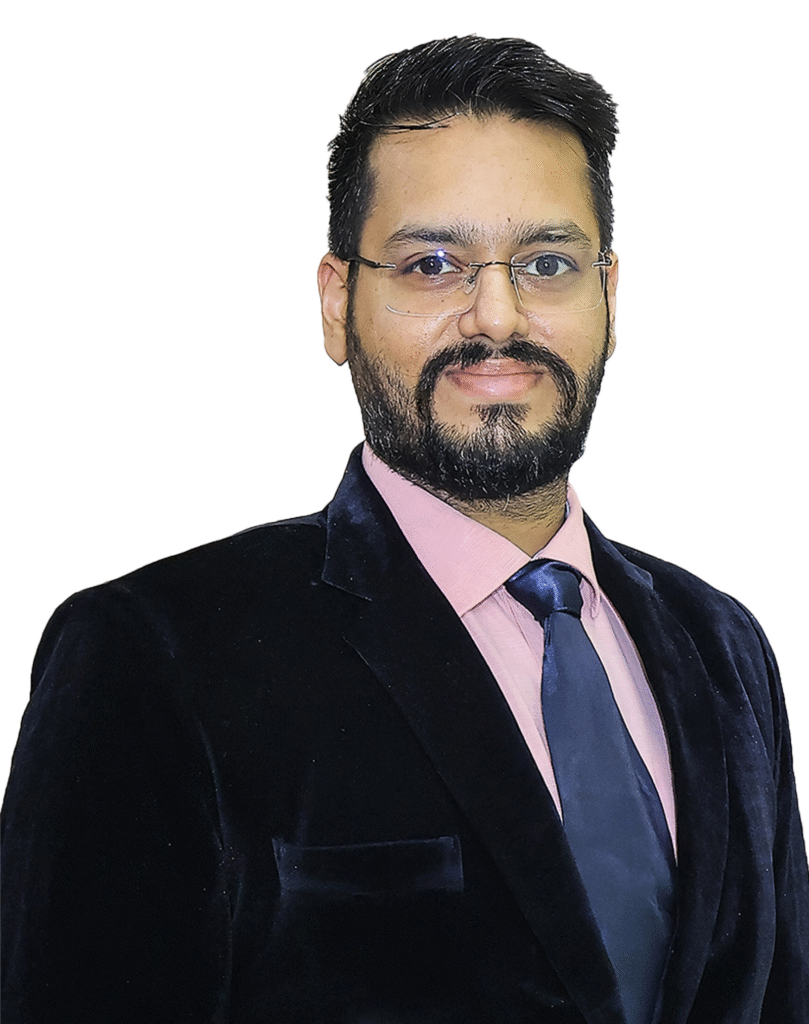

The Department of Orthopaedics & Joint Replacement at Wadi Hospital, Bathinda, is a state-of-the-art center delivering advanced orthopedic care with compassion, precision, and excellence. Under the leadership of Dr. Meet Kamal Wadi (M.B.B.S., M.S. Ortho) – a renowned orthopedic surgeon with over a decade of experience – the department has become a trusted destination for comprehensive musculoskeletal care.

Related Doctors